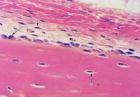

長骨磨片示骨單位的光鏡結構

哈弗斯系統水平面骨單位是長股骨幹內主要起支持作用的結構和營養單位,呈長筒形,長0.6~2.5nm,直徑30~70微米,約有十數層骨板圍成。長骨骨幹主要由大量與骨長軸平行排列的孤單位組成。各層骨板間的骨陷窩和骨小管相互通連,最內層骨小管開口於中央管,館內有骨膜結締組織及血管和神經,骨細胞從中央管內的組織液獲得營養並

排出廢物。相鄰骨單位之間可見粘合線,它是一層含鹽多、含纖維少的骨基質,構成骨單位的邊界,相鄰骨單位的骨小管在粘合線處互不通連。相鄰骨單位的中央管相互間以橫行的穿通管相通連。